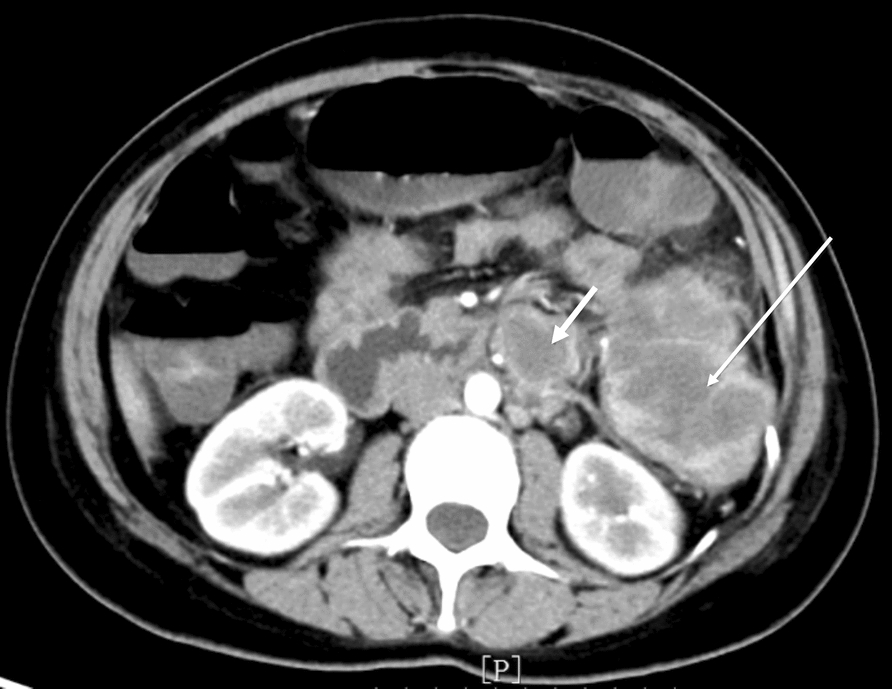

Case presentation: Herein, we report a case of a 37-year-old Chinese woman diagnosed with postpartum descending colon squamous cell carcinoma harboring the BRAFV600E mutation, which was treated with radical resection and adjuvant chemotherapy combined with targeted therapy. Eight months later, a new lesion was detected in the colon 40 cm away from the first mass. The patient was enrolled in a clinical trial but withdrew following two treatment cycles because of rapid disease progression. Subsequently, the patient died approximately 6 months after enrolling in the trial.